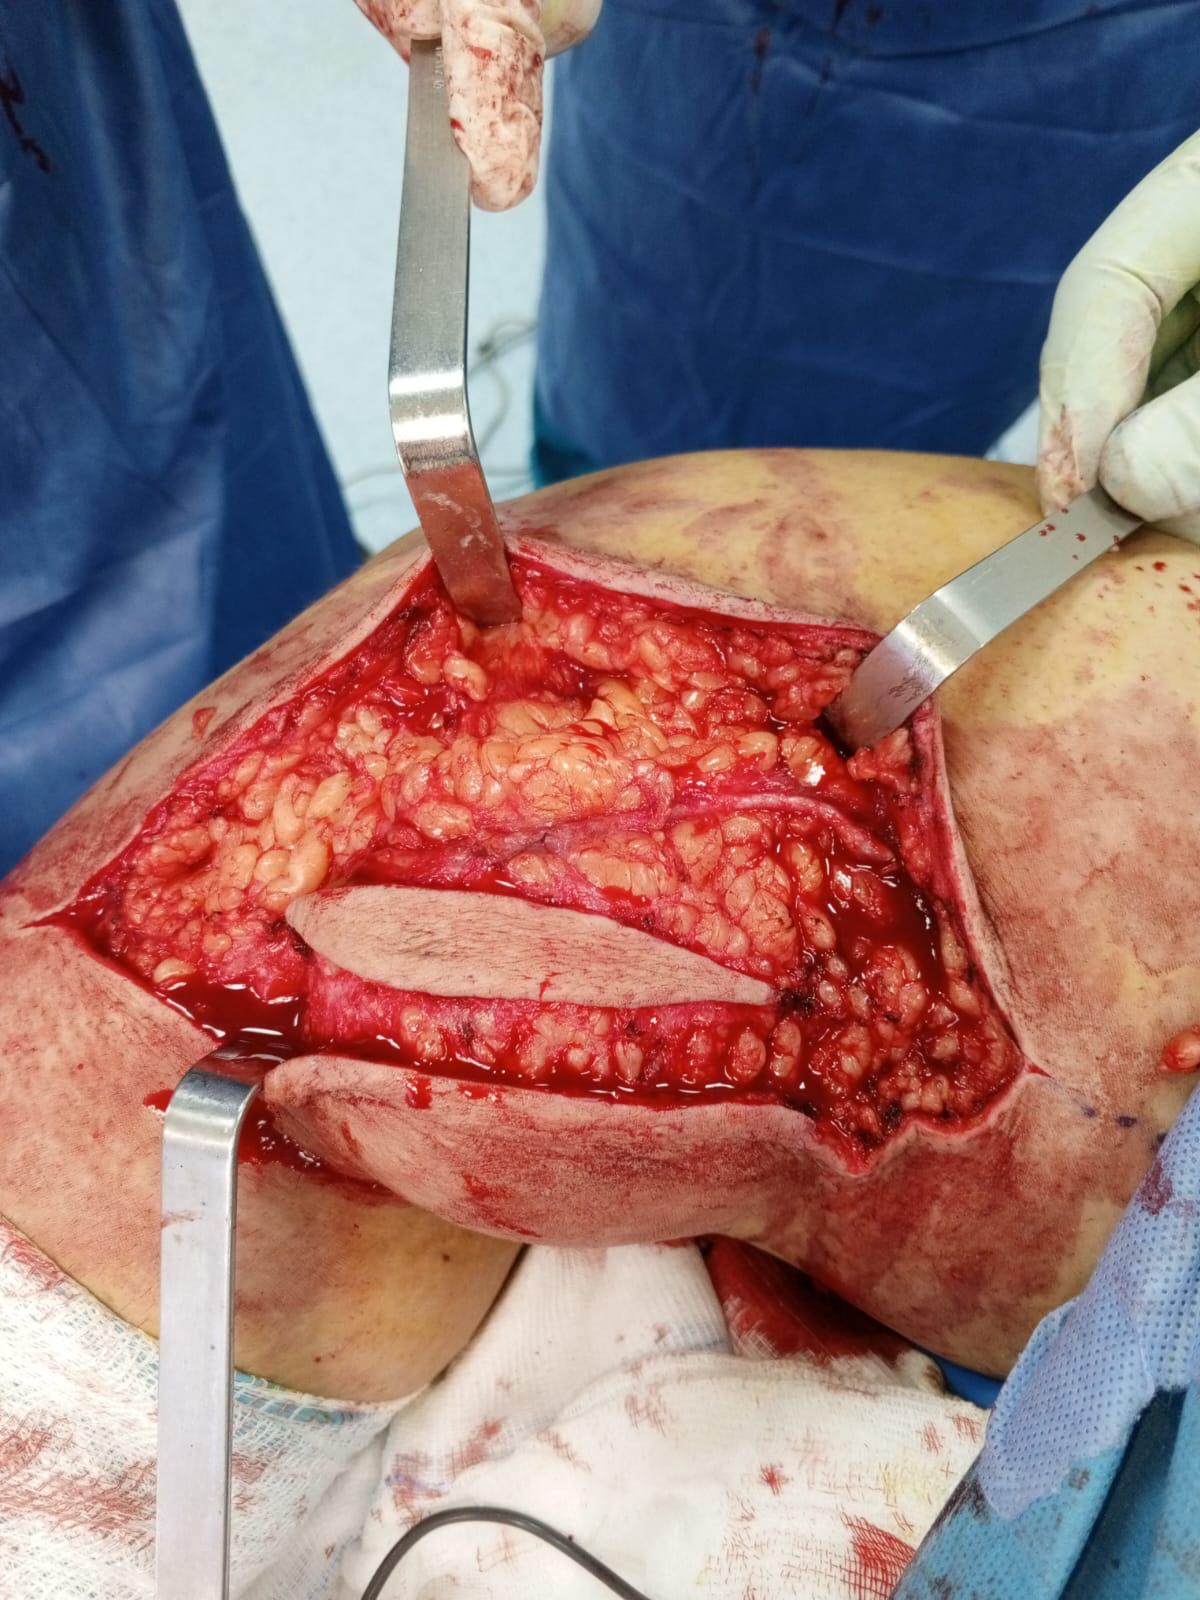

Muscle Cancer